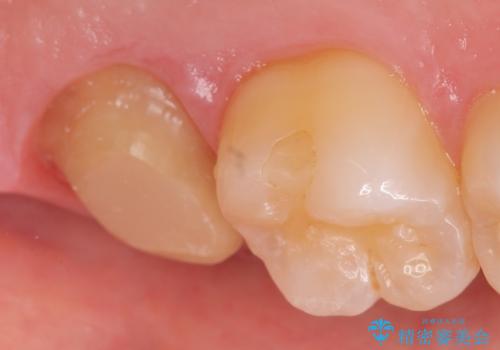

診査の結果左上7は神経が死んでいたため、根管治療を行いました。

症状の緩解を確認後、オールセラミッククラウンによる補綴を行いました。

今回用いたオールセラミッククラウンはジルコニアフレームという白い素材の上にセラミックを盛っているため、審美性が非常に高いのが特徴です。

また、ジルコニアは人工ダイヤモンドの材料にも使われているほど高い強度を持っており、そのためオールセラミッククラウンは審美性だけでなく、奥歯やブリッジの補綴も可能とするクラウンです。